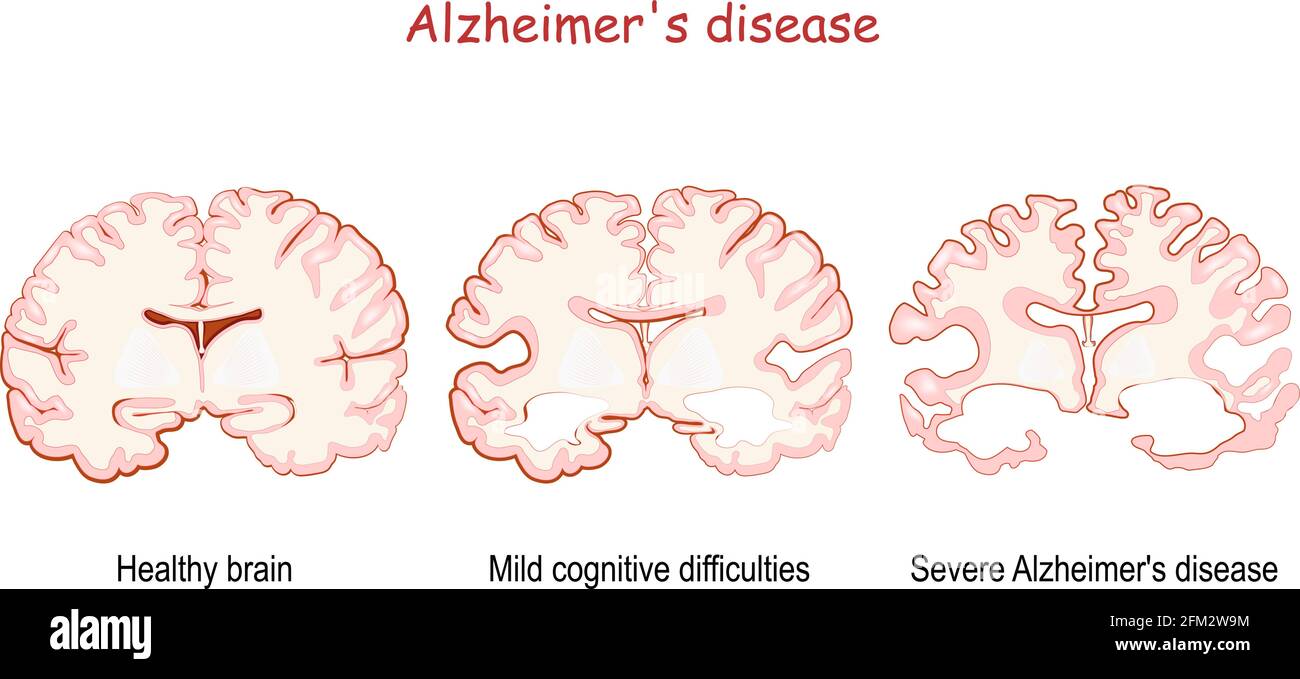

RF2XARW8C–Morbo di Alzheimer. Neurodegenerazione. Sezione trasversale del cervello normale e Alzheimer, con atrofia della corteccia cerebrale, ventricoli ingrossati e Hipp

RF3BH7B1F–Morbo di Alzheimer. Neurodegenerazione. Sezione trasversale del cervello di Alzheimer, con atrofia della corteccia cerebrale, ventricoli ingrossati e ippocampo. Un

RF2FM2W9M–L'Alzheimer, è una malattia neurodegenerativa. Demenza. Confronto e differenza tra cervello sano, morbo di Alzheimer grave e cognitivo lieve